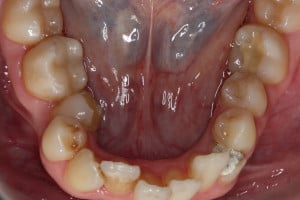

Młoda pacjentka zgłosiła się do naszego gabinetu celem wykonania kompleksowego leczenia zachowawczo-ortodontycznego. Oprócz problemów natury ortodontycznej stwierdzono złą higienę jamy ustnej oraz liczne potrzeby leczenia zachowawczo-endodontycznego. Po wnikliwej analizie telerentgenowskiej oraz analizie modeli zadecydowano o ekstrakcji 2 zębów w łuku dolnym (kła po stronie lewej oraz pierwszego przedtrzonowca po stronie prawej). Plan leczenia obejmował ponadto zamknięcie łuku po brakujących zębach w łuku górnym. Leczenie aktywne trwało 2 lata i 8 miesięcy. W czasie jego trwania pacjentka była regularnie poddawana zabiegom higieny profesjonalnej celem eliminacji zapaleń przyzębia brzeżnego. Po leczeniu aktywnym zastosowano leczenie retencyjne w postaci retainera stałego w żuchwie oraz szyny retencyjnej w łuku górnym.